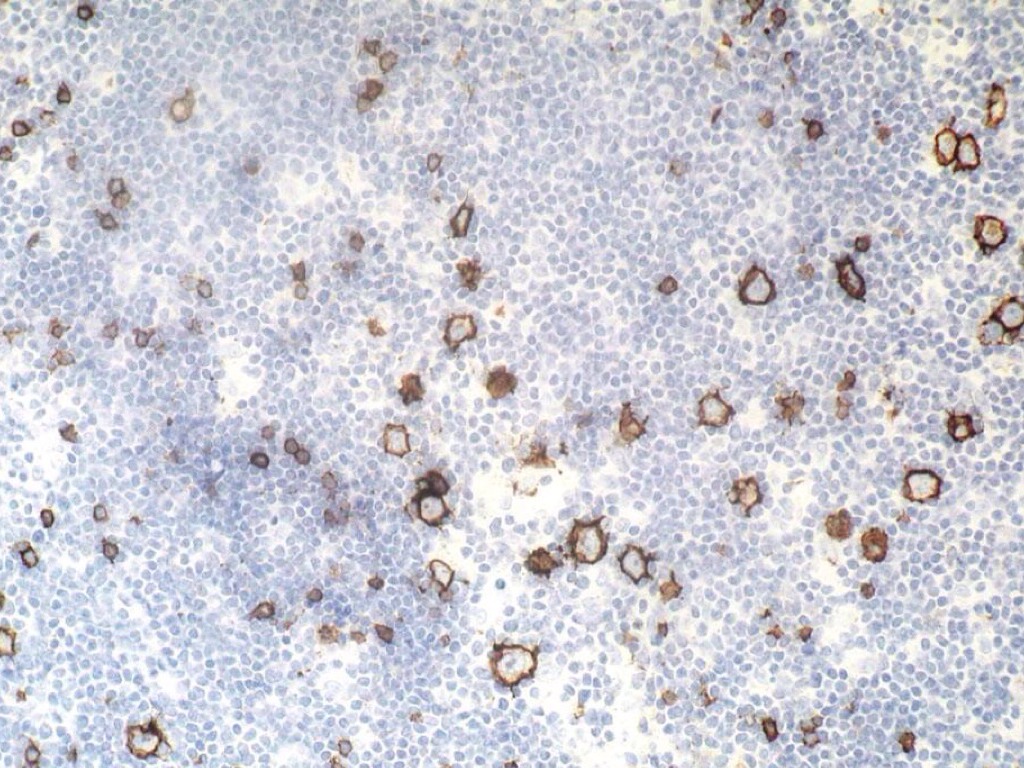

Untitled Slide

CM

• Mezcla de células de Reed-Sternberg con células no neoplásicas

• Neutrófilos

• Histiocitos

• Células plasmáticas

• Eosinófilos y linfocitos

EXPRESAN

• Cd20+\-

• EMA (antígeno epitelial de membrana)

• Cd15

• Cd30

• VEB 40-70%